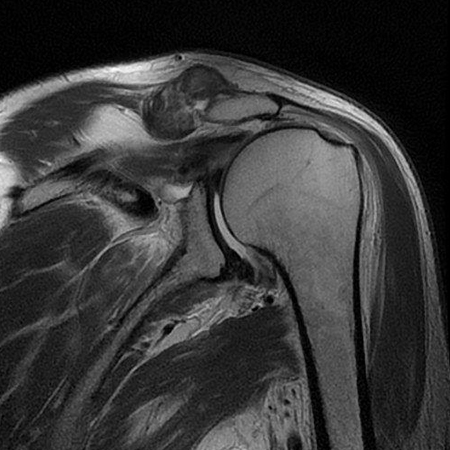

Rotatorenmanschettenriß in der Kernspintomographie

Die Erkrankung der Sehnen kann von einer Aufrauhung über eine Teildurchtrennung bis hin zum vollständigen Abriss der Sehnen reichen. Durch eine klinische Untersuchung mit spezifischen Funktionstests zur Beweglichkeit und Kraft sowie bildgebenden Untersuchungen wie Röntgen, Ultraschall und Kernspintomographie kann ein genaues Gesamtbild der Situation im Rahmen der Sprechstunde erstellt werden.

Der Patient berichtet, dass er beim Volleyballspiel beim Überkopfaufschlag eine Schultergelenksverrenkung (Luxation) erlitten habe. Er habe bereits zuvor leichte Beschwerden gehabt. In der Kernspintomographie zeigte sich ein Sehnenabriss an der Supraspinatussehne wie auch eine Kapselverletzung am vorderen unteren Gelenk. Arthroskopisches Vorgehen mit Rekonstruktion der Läsionen. Der Patient demonstriert nach 6 Monaten im Januar 2022 eine stabile Schulter im Rahmen der Liegestütze. Eine Wiederaufnahme des Volleyballspielens ist im Weiteren geplant.

62-jährige Patientin mit erheblichen Schmerzen und vollschichtiger Supraspinatussehnenablösung. Die Sehne war sehr weit zurückgezogen, bereits sichtbar auf der präoperativen Kernspintomographie und ließ sich auch intraoperativ nicht so weit mobilisieren. Eine Rekonstruktion war spannungsarm nicht möglich. Es wurde ein mit Flüssigkeit gefüllter Ballon unter dem Schulterdach arthroskopisch gestützt eingeschoben und entfaltet. Dieser Ballon führt neben einer Abstandshaltung zum Schulterdach zu einer Fremdköperreaktion und Membranbildung. Durch die anhaltende Trainingstherapie konnte die Patientin trotz des Defektes eine Rezentrierung des Gelenkes mit sehr guter anhaltender Funktion erzielen.